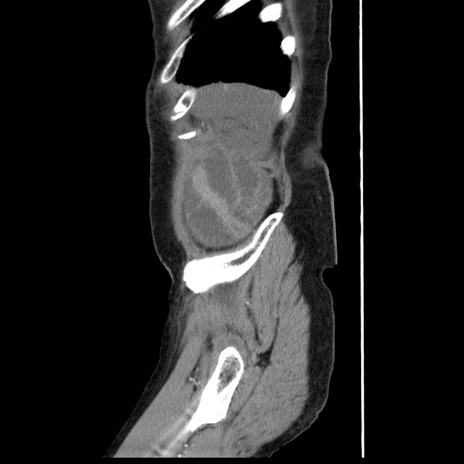

横断像

【症例】80歳代女性

【主訴】腹痛

【現病歴】8時間前から腹痛あり来院。

【既往歴】糖尿病、脂質異常症、子宮体癌にて子宮全摘術

【身体所見】意識清明・会話良好だが腹痛で苦悶様、全腹部にわたって反跳痛と圧痛あり

【データ】WBC 13600、CRP 0.14、LDH 224、CK 90